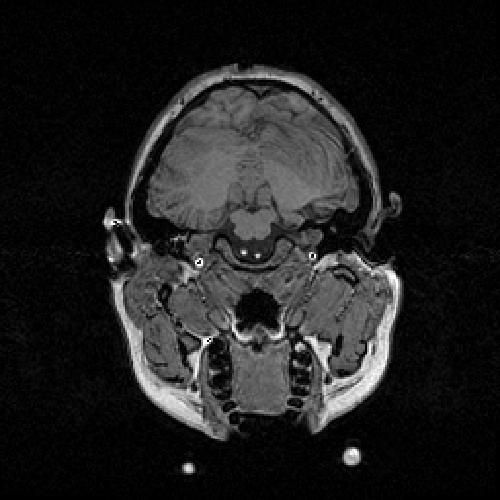

Anatomical information is required to model the visual cortex more realistically and magnetic resonance imaging (MRI) is well suited to this purpose. Cortical features were obtained from T1 weighted MR scans taken in a 1.5 Tesla field in order to maximise contrast between white matter and grey matter. Coronal scans of the entire head were taken 1.5 mm apart with contiguous spacings of 1.0 mm. A total of 118 slices, each 256x256 pixels, were obtained. Here is an example of a single MR slice.

MR Slice